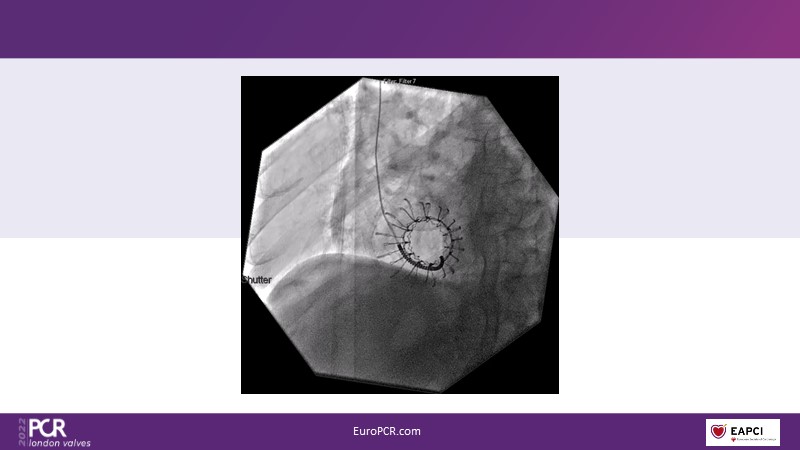

The right valves for the right ventricle: Venus MedTech tricuspid and pulmonary replacement systems

In this session from PCR London Valves 2022, discover the new Venus MedTech technology for tricuspid and pulmonary valve replacement, and a review of the clinical indications, selection criteria and procedural details.

- To learn about Venus MedTech technology, clinical indications and procedural details of valve replacement systems

- To learn more about the clinical experience and outcomes with Cardiovalve tricuspid and Venus P-valve